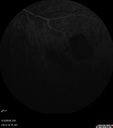

51 year old male with a broken vein in the left eye. His vision is pretty good. He has not noticed any vision change. You asked him to come here for further evaluation in the left eye. VA OD: sc20/63 PH20/25-2 NccJ1 VA OS: sc20/20 Patient had scatter laser to non-perfused retina and never had a vitreous hemorrhage (yet)

Coats' Disease -51 year old asymptomatic male450 views20/20 vision - had laser to non-perfusion because of proliferation.00000